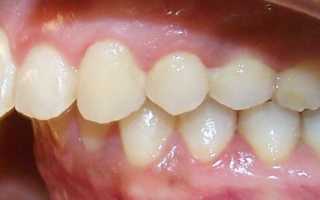

Фото 1. Дистальный прикус характеризуется более развитой верхней челюстью.

Дистальный прикус как самостоятельный тип встречается редко. В 80% случаев наблюдается сочетание 2-х патологий: прогнатического и глубокого прикусов, когда верхние резцы перекрывают нижние больше, чем на половину. Как правило, отсутствует контакт между фронтальными зубами на обоих челюстях.

Дистальный прикус — это состояние, при котором верхние зубы расположены значительно впереди нижних. Врачи отмечают, что его можно обнаружить при визуальном осмотре: если при закрытии рта верхние резцы перекрывают нижние более чем на один сантиметр, это может быть признаком проблемы. Кроме того, пациенты могут испытывать трудности с жеванием и говорить о дискомфорте в области челюсти.